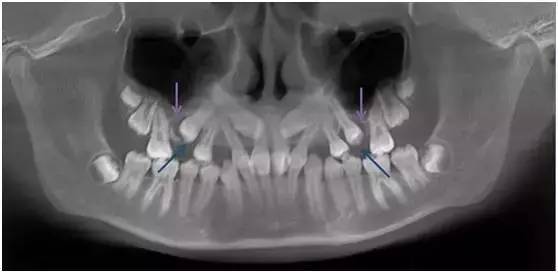

局部解剖异常

局部解剖异常造成牙齿萌出受限在临床上比较少见,但治疗难度比较大,而且往往需要多学科配合。

下面这位患者就是因为上颌窦气化过于充分,窦底接近牙槽基骨的顶端(如图紫色箭头处),造成双尖牙区域牙槽基骨骨量不够,第二双尖牙无法正常萌出(如图蓝色箭头处)。

这种情况即使进行正畸治疗,也会因为局部骨量不够,出现第二双尖牙无法牵引到位或根周骨量不够的风险。